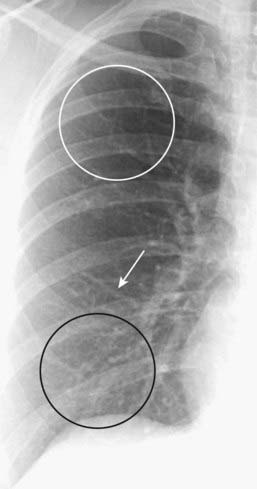

image

Figure 9-8 Normal pulmonary vasculature.

The right lung is shown. The lower lobe vessels (black circle) are larger in size than the upper lobe vessels (white circle) in the upright position, and all vessels taper gradually from central to peripheral (white arrow). Alterations in pulmonary flow or pressure may change these relationships.